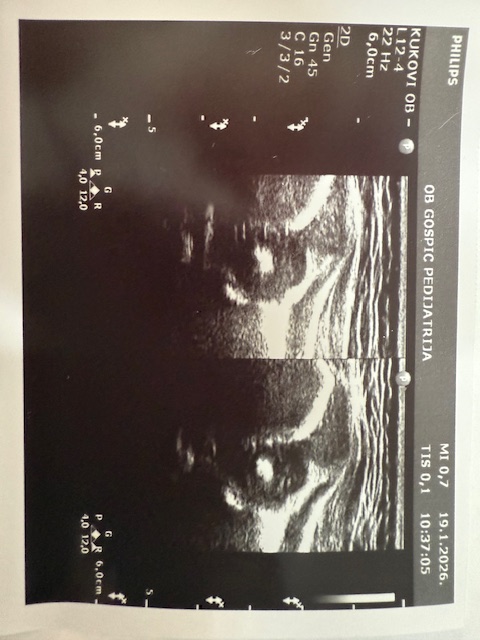

Dječji odjel opće bolnice Gospić jedan je od manjih u Hrvatskoj, ali izuzetno aktivan. Uz redovnu djelatnost, ambulante, Dnevne bolnice i vođenja samog Odjela kao i Rodilišta što obavljaju tri liječnice specijalisti pedijatrije (Sandra Čubelić, dr.med., Linda Hibravi Kosić, dr.med. i Kristina Ilić, dr.med.), pri Odjelu radi i Ultrazvučna ambulanta u kojoj se već 20 godina jedini u Hrvatskoj radi dojenački probir na bolesti i razvojne poremećaje mozga i razvojni poremećaj zgloba kuka. Dakle naglašavamo da svako dojenče rođeno u Općoj bolnici Gospić obavi oba ova pregleda po principu “skrininga”, što znači da se traže poremećaji kod zdrave djece.

Probir radi pedijatrica i ravnateljica bolnice, dr. Sandra Čubelić, a analizom je utvrđeno kako se uz ovaj nadstandard koji imaju djeca Ličko-senjske županije godišnje odradi oko 1200 ultrazvučnih pregleda, odnosno tijekom ovih 20 godina učinjeno je oko 25000 pregleda. U početku su se pregledi radili još u novorođenačkoj dobi, a sada je uobičajeno napraviti pregled dojenčadi u dobi od 1 mjesec. Svrha navedenog je otkriti poremećaj prije nego što se kod djeteta pokažu simptomi i znakovi bolesti stoga valja istaknuti da je kod dvoje djece izvedena operacija mozga prije nego je dojenče imalo ikakve poremećaje u smislu smetnji psihomotornog razvoja dok različite se manje razvojne poremećaje nađe bitno češće.

Što se tiče zgloba kuka, razvojni poremećaji se graduiraju pa se teži poremećaji kao što je luksacija i subluksacija nađu rjeđe, dok se poremećaji u smislu displazije nađu češće, a svrha ovih pregleda je da se izliječe prije prohodavanja djeteta jer poremećaji koji se uoče nakon što dijete prohoda se teže i dugotrajnije liječe, čak i operativno.